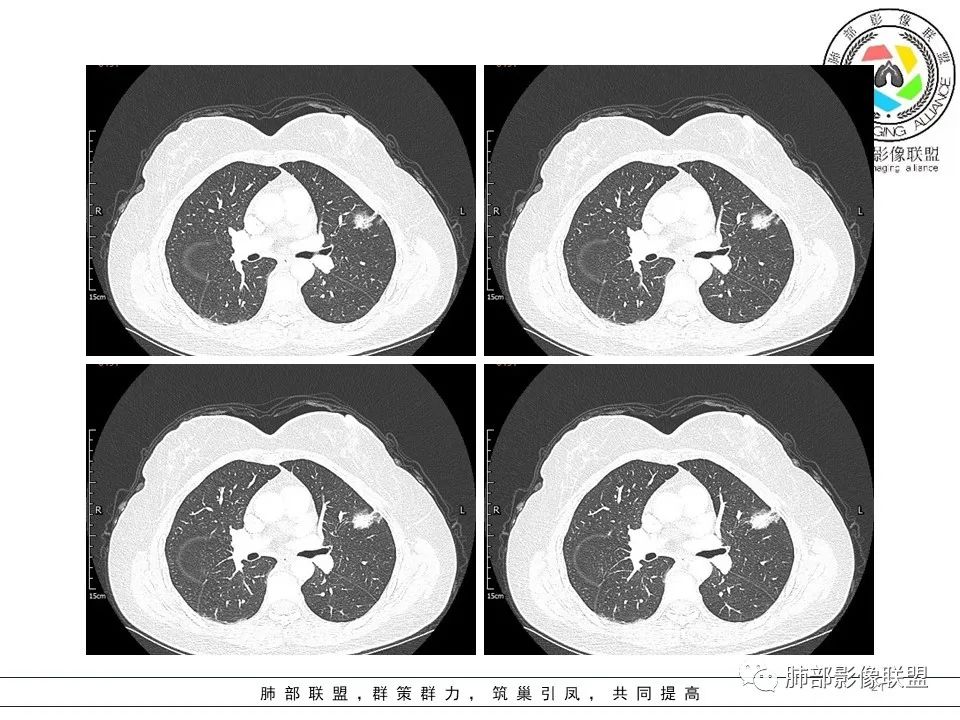

左肺上叶腺癌1例CT影像讨论

一.大结节影像特点:

左肺上叶胸膜下不规则结节影,分叶、粗短毛刺,胸膜牵拉等,像个“刺头”。 医学百科网 | YxBaike.Com

未见钙化,也未显示液化坏死或空洞。 医学百科网 | YxBaike.Com

与支气管相关,但取层未能显示支气管进入情况。 医学百科网 | YxBaike.Com

1.病灶周围向几个方向膨出的边界清楚的磨玻璃影,这些磨玻璃影时隔几个月依然,几乎可以排除出血及一般的炎性改变。

2.病灶的胸膜牵拉线与其间病灶胸膜侧的磨玻璃边构成朝向胸壁的“月牙铲”结构,这种影像学表现某种程度上反映出病理学特征——病灶收缩 小叶间隔阻挡。 医学百科网 | YxBaike.Com

3.病灶实性密度区强化明显,这有助于我们区分一些其他类似病灶,如结核灶等! 医学百科网 | YxBaike.Com

4.邻近未见树芽征及卫星灶等。

结合临床,应当高度怀疑浸润性肺腺癌!